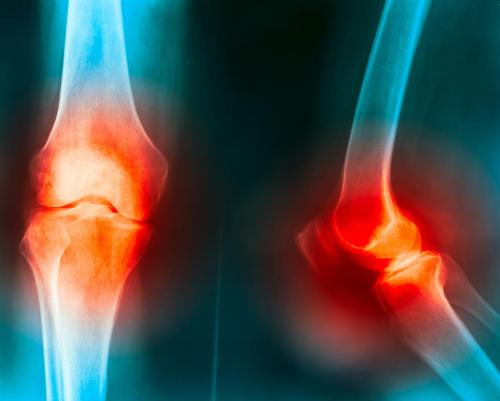

早期表现为膝关节内侧疼痛,X光片上膝关节内侧间隙变窄、边缘增生、硬化。病人早期只是在一些较用力动作时感到疼痛,比如上下楼、蹲下站起等,但经休息就有所恢复,如果不早期治疗,病变会进一步发展。到了中期走路开始疼,腿别扭,疲劳感加重,发病部位酸痛。

典型的膝关节退行性骨关节炎症状是膝关节疼痛、关节变形、变大、变粗、反复肿胀,有时关节活动会产生杂音、弹响,甚至铰锁、活动受限等等。患者常抱怨无法蹲起,尤其是上下楼梯无力,疼痛。